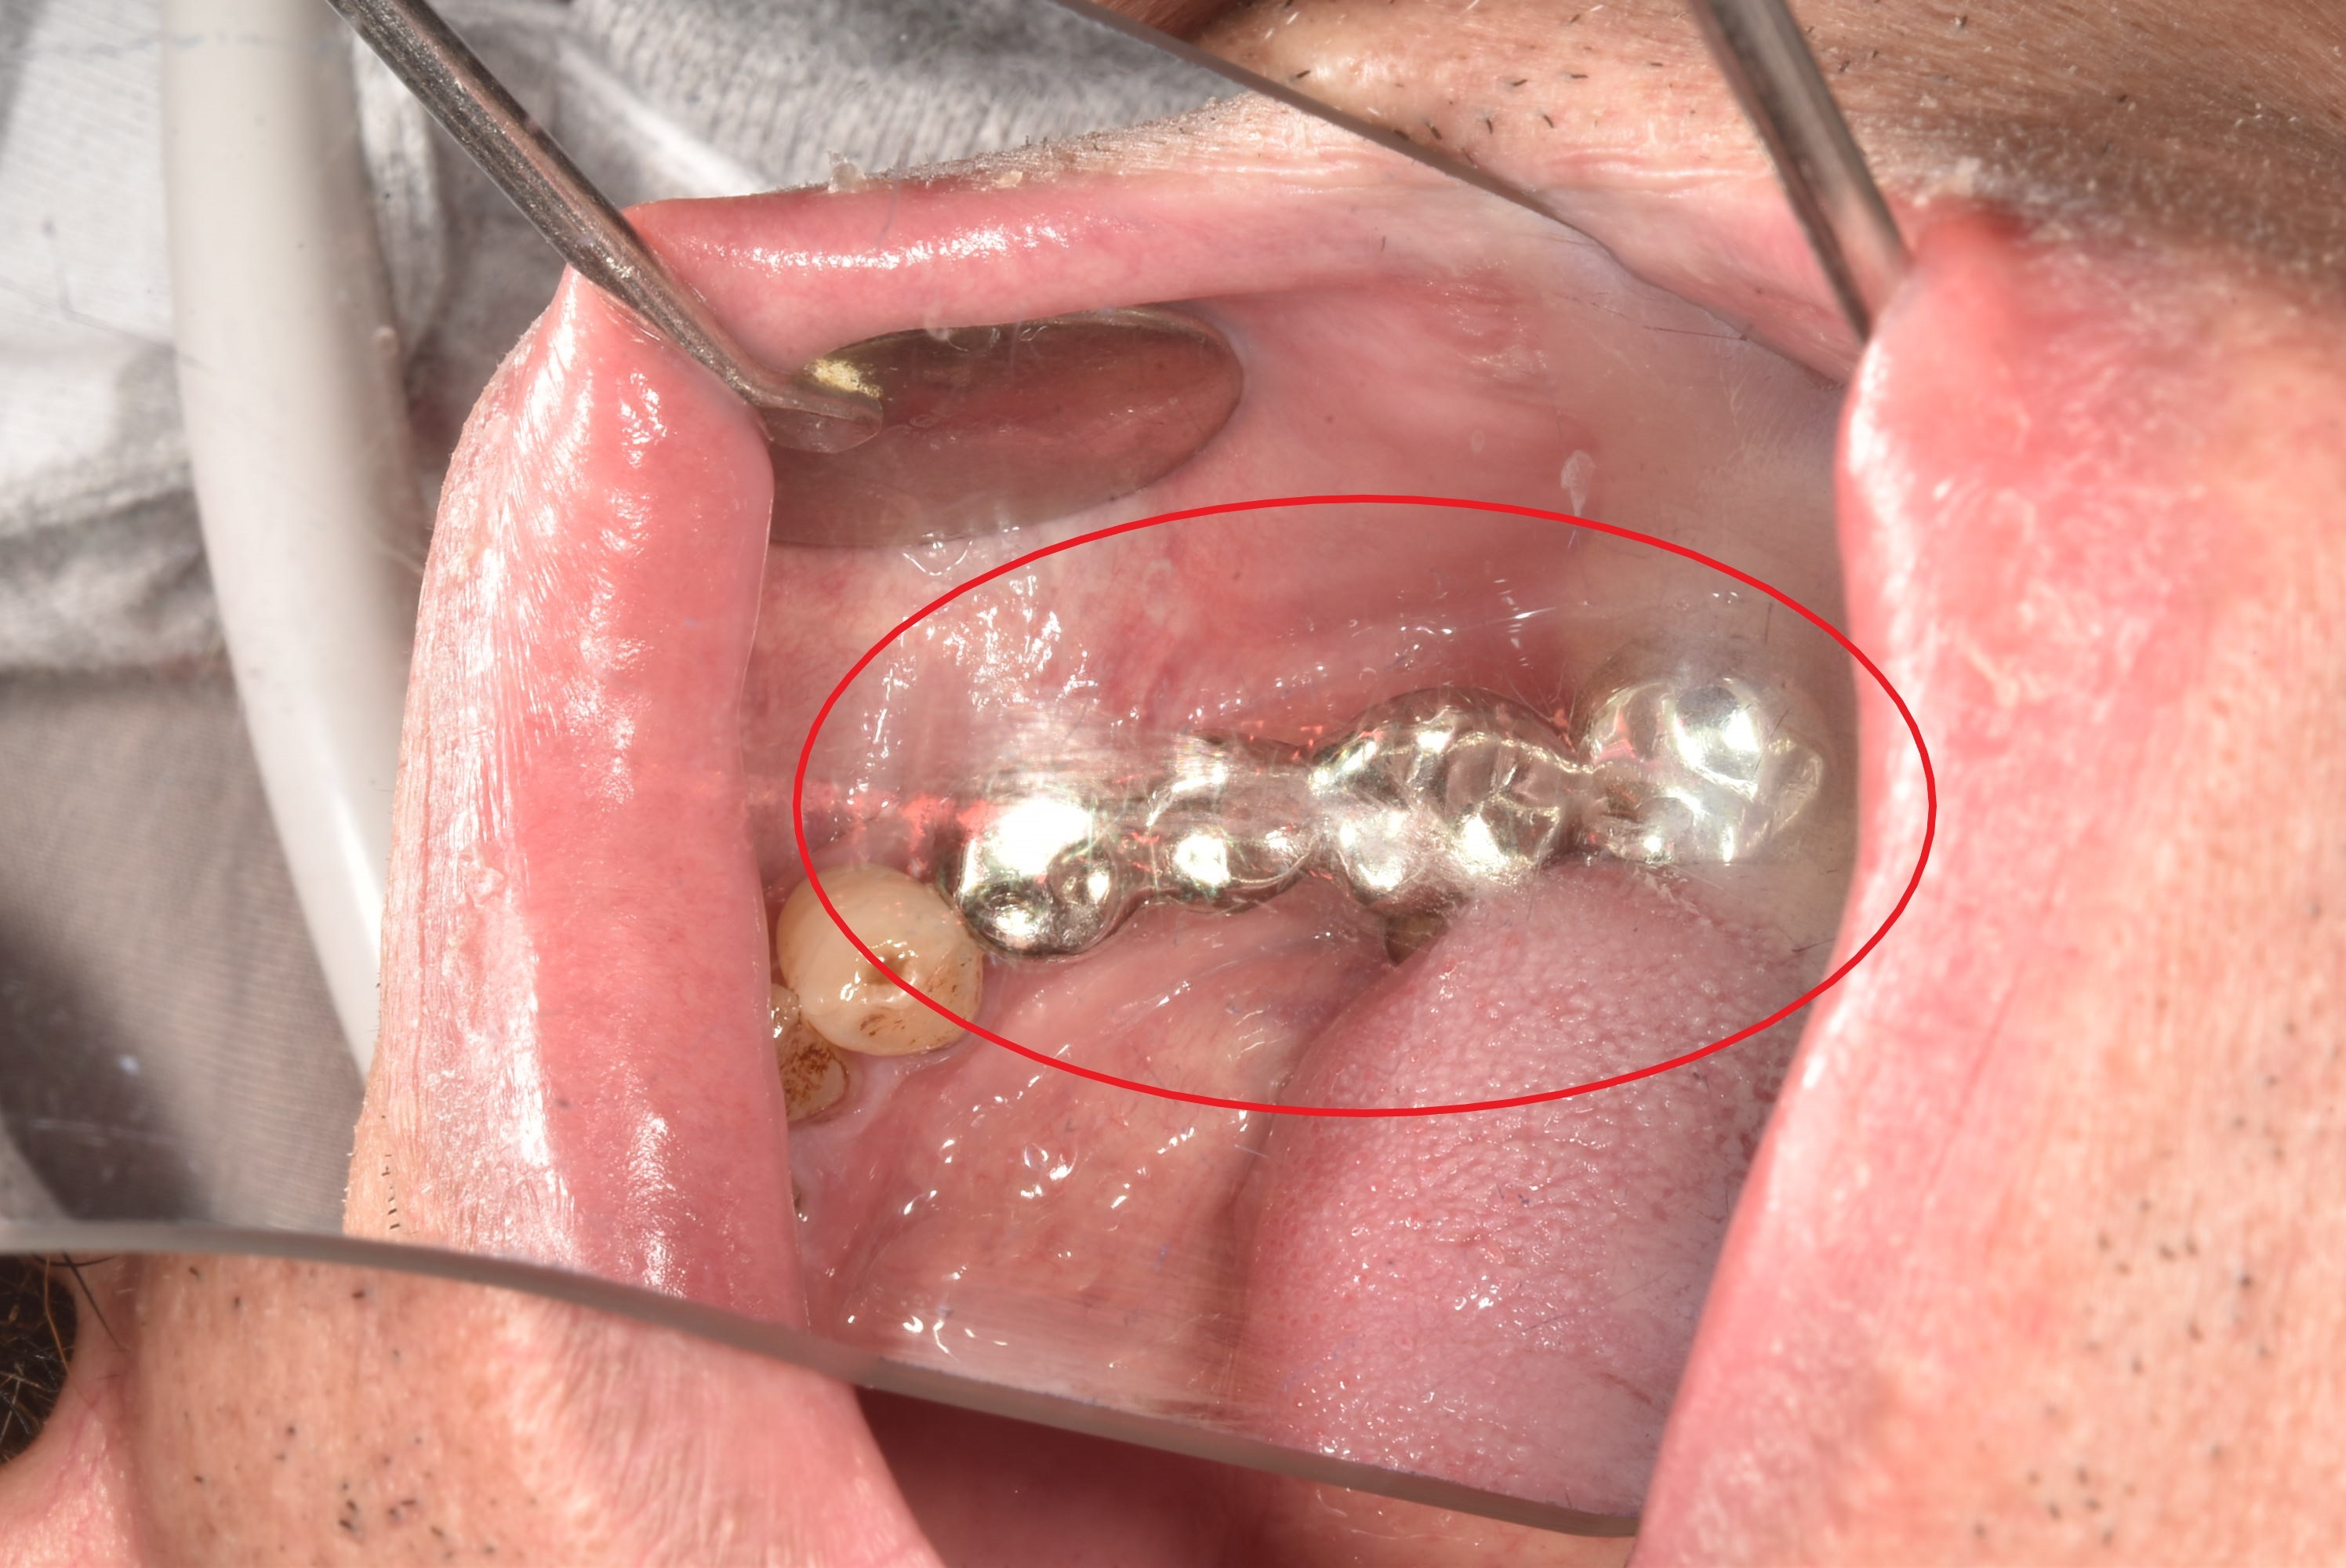

案例二

立即拔除壞牙根

當天完成植牙手術,並鎖上癒合螺帽

2-3月癒合,取下癒合螺帽,透過數位口掃至技公所製作假牙

7-10天完成假牙,試戴、調整咬合高度並鎖上,封填,完成